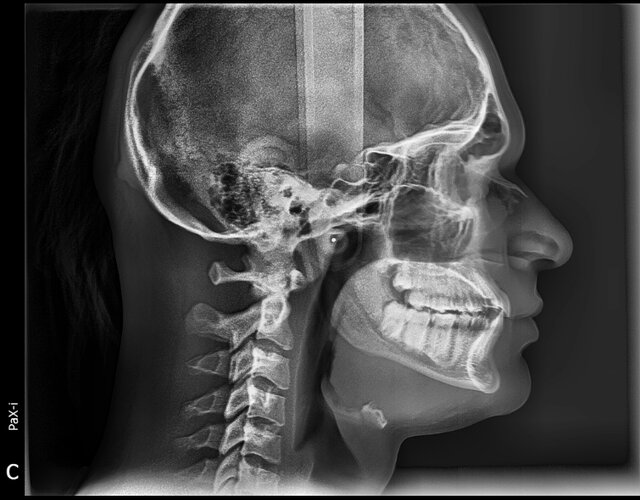

C